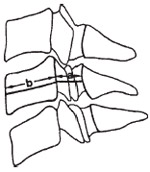

A relação com estenose foi demonstrada tanto quanto feitas as medidas de forma absoluta, como quando avaliado o chamado índice de Torg, que, quando menor do que 0,8, indica estenose (figura 6).

Fig. 6– Desenho esquemático representando a m edida do índice de Torg

Consideramos que o índice de Torg é extremamente importante, pois elimina as distorções na medida do diâmetro, que podem ser provocadas por alterações nessa distância entre a ampola e o filme, evitando a necessidade do uso dessas tabelas complexas de avaliação e simplificando a análise das radiografias. A medida do índice de Torg tem metodologia simples e reprodutível por diferentes examinadores, consistindo na relação entre o diâmetro do canal cervical, em determinado nível, sobre a medida do diâmetro ântero-posterior da vértebra no mesmo nível, ambos tomados na metade da altura da citada vértebra. Essa avaliação pode ser empregada não só no trauma raquimedular, como na análise das estenoses congênitas e degenerativas, ou como parte do exame dos candidatos à prática de esportes de contato que ofereçam risco de acidentes envolvendo a coluna cervical, como o futebol americano e o rúgbi.